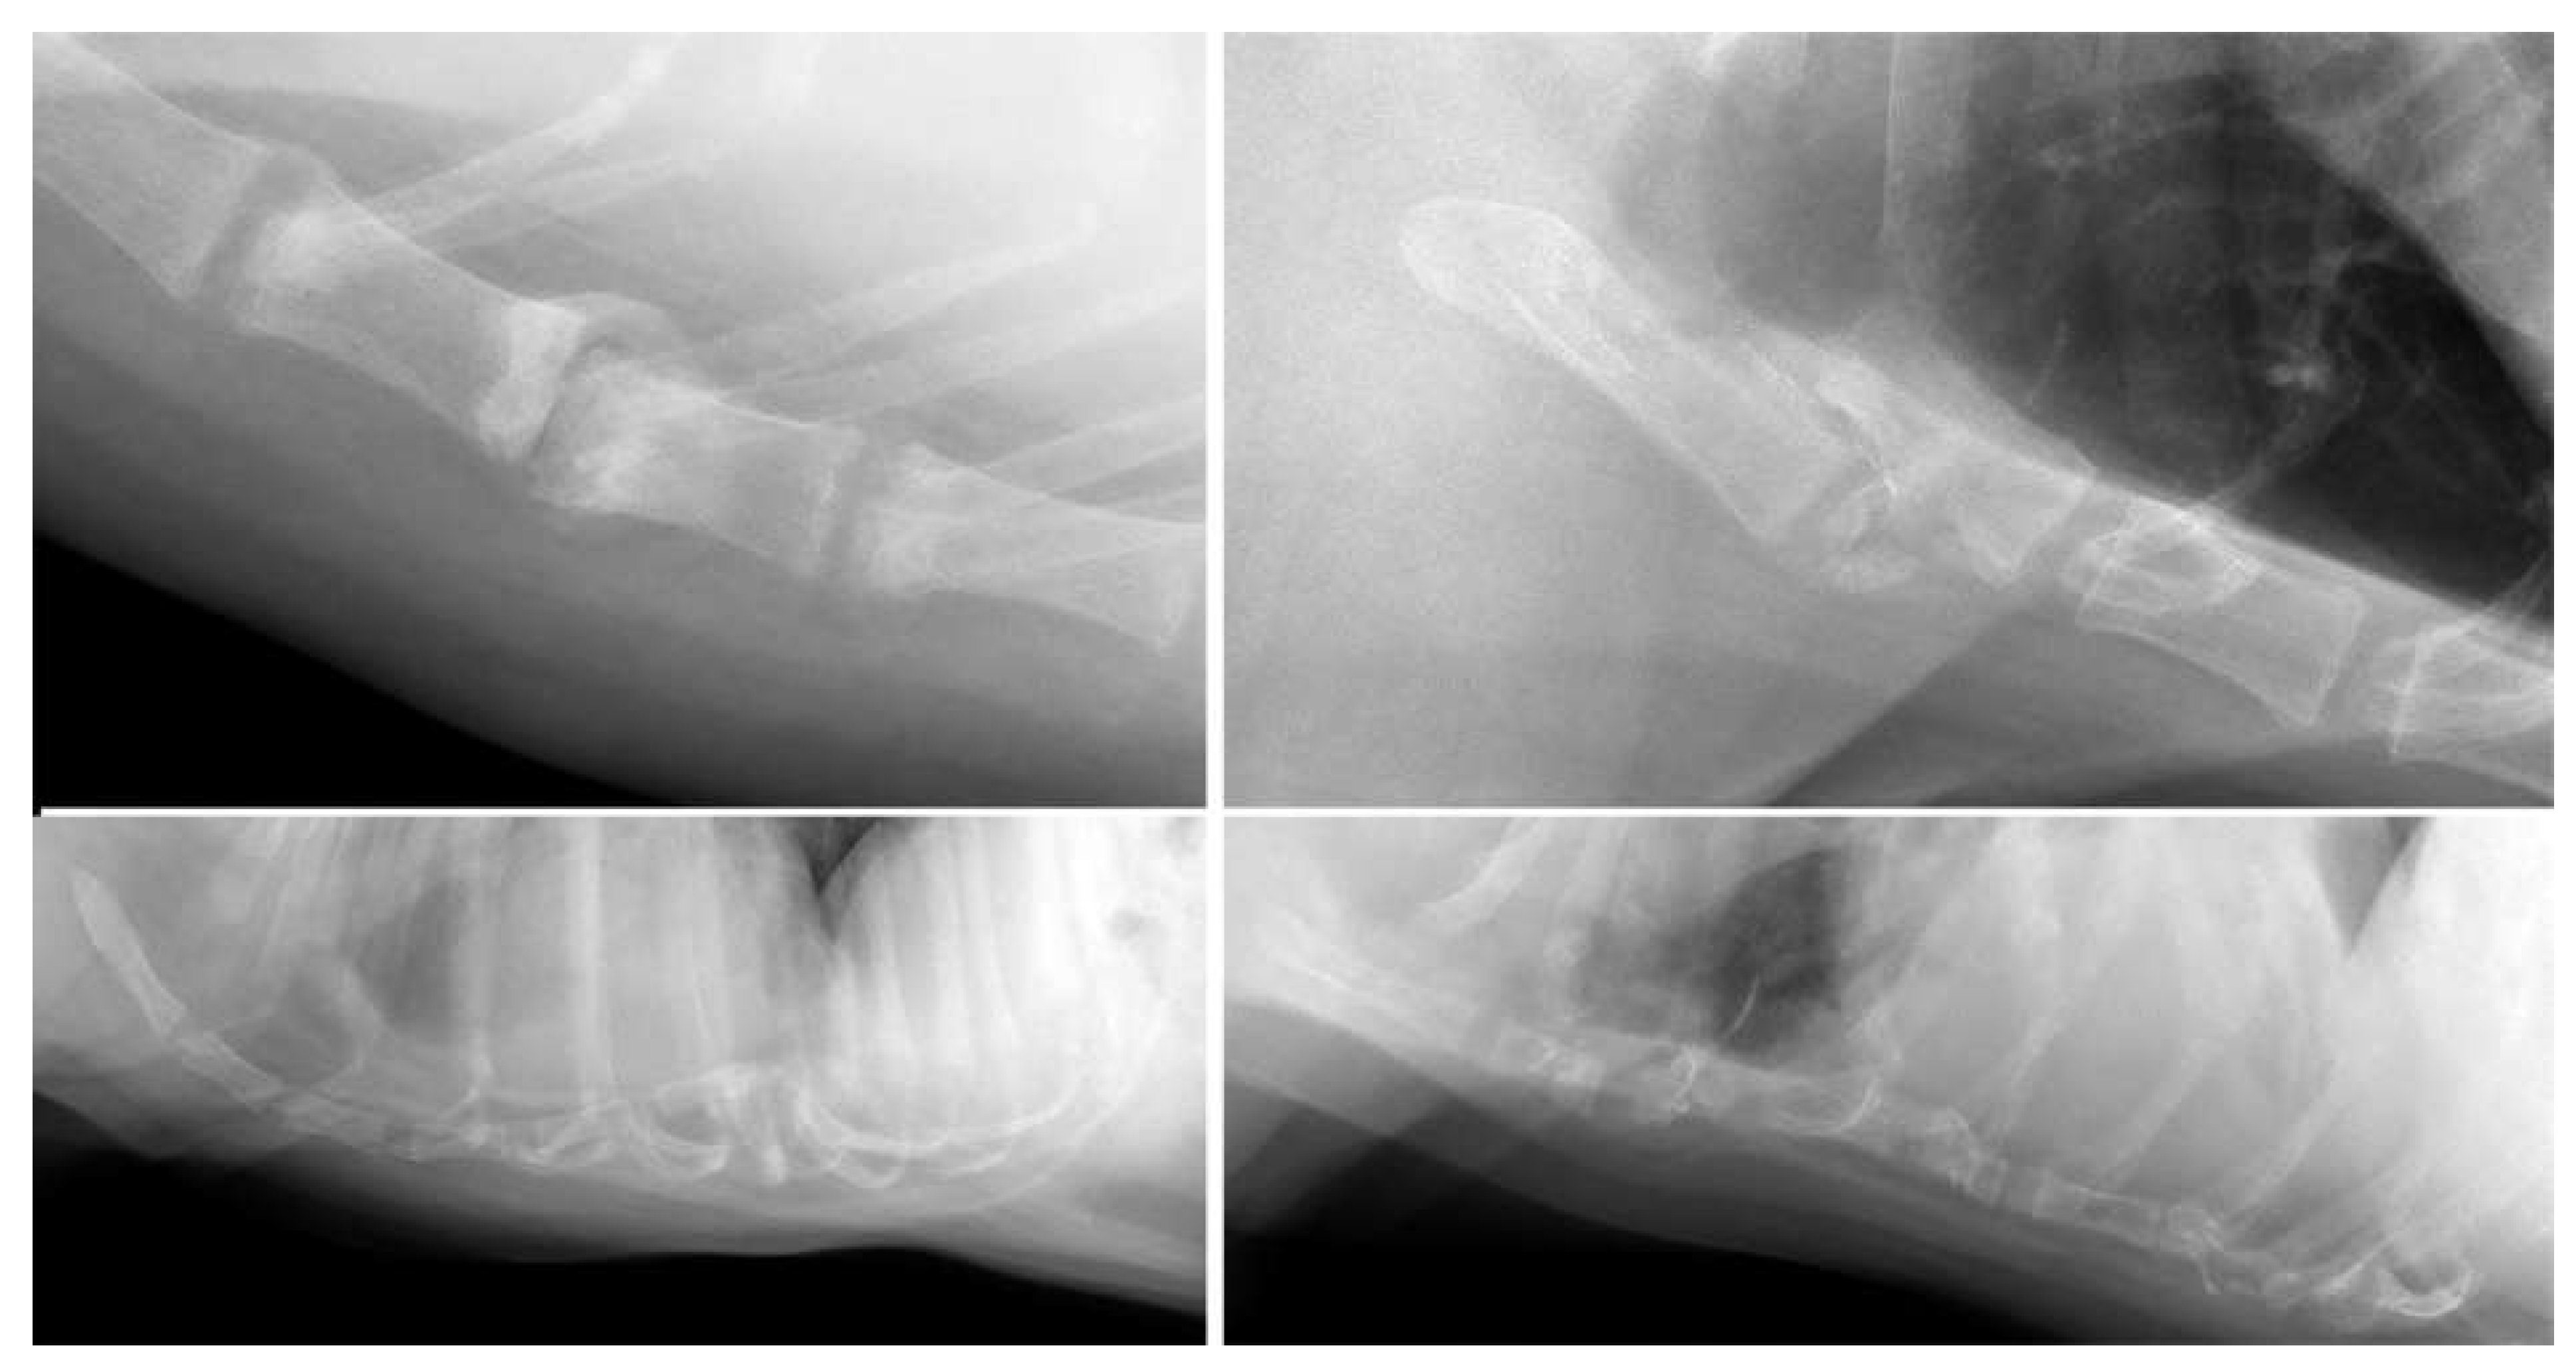

3.1. Dogs

3.2. Cats

| Post-trauma (n = 12) | Dislocation (n = 5); collapse (n = 8); fracture (n = 2) | Labrador Retriever (3/62); mixed (2/145); Alaskan Malamute (1/4); Boxer (1/13); Chihuahua (1/28); Chow Chow (1/3); German Shepherd (1/21); Labradoodle (1/22); Welsh Springer Spaniel (1/3) |

| Aggressive bone lesion (n = 2) | Osteolysis; pathological fracture | Chihuahua (n = 1); Labradoodle (n = 1) |